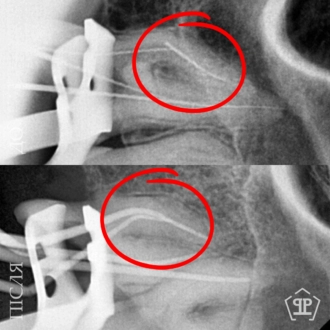

Показательный кейс одноэтапной имплантации All-on-6 на верхней челюсти. Импланты установлены в кости под углом, минуя гайморовые пазухи.